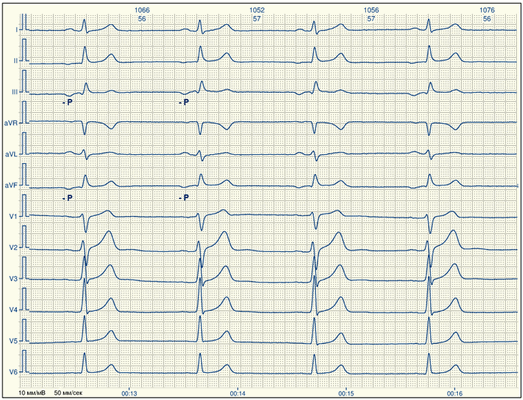

Признаки на ЭКГ

- Неравные интервалы P-P, также и P-Q.

- Изменение ЧСС в сторону увеличения или уменьшения. Брадикардия следствие перемещения функциональной активности в атриовентрикулярный узел.

- Деформации зубца P. При каждом сокращении он имею разную полярность, вид.

Миграция водителя ритма на ЭКГ определяется изменением специфических комплексов и относительно просто диагностируется при должной квалификации.

Патология на кардиограмме характеризуется:

- нарушением формы и продолжительности зубца Р;

- уменьшением частоты сердечных сокращений;

- изменением интервалов PQ;

- укорочением или замедлением интервала RR.

В рамках данного курса, мы не будем углубляться в виды суправентрикулярного ритма (правопредсердный, левопредсердный, узловой, нижнепредсердный, ритм венечного синуса и т.д.). О них достаточно много сказано в специализированных изданиях. Для вас, как врача не кардиолога, а именно для этой группы врачей создан этот курс, достаточно будет запомнить, что все ритмы исходящие выше разветвления ножек пучка Гиса считаются суправентрикулярными. Для них характерно (упрощенные правила):

- Ритмичность, частота сердечных до 100 ударов в минуту.

- Наличие отрицательного зубца Р’ в отведениях II, AVF до или после желудочкового комплекса QRS на одинаковом расстоянии.

- Иногда зубцов Р может быть не видно так как они накладываются на комплекс QRS.

Фактически, Вы видите на ЭКГ ритмичную работу сердца, но вместо привычных синусовых Р («P+» aVF, II), Вы видите Р не синусового происхождения.

Давайте посмотрим как это выглядит (ЭКГ с суправентрикулярным ритмом):

На ЭКГ мы видим отрицательные зубцы Р’ идущие перед желудочковыми комплексами (QRS). Если вы вспомните признаки синусового ритма, то там в этих отведениях зубцы Р всегда положительные.